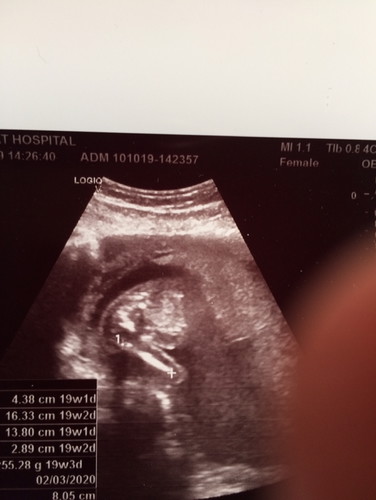

ผลอัลตราซาวด์

น้องอวัยวะครบไหมคะ 19 วีค แม่ท่านไหนดูออก